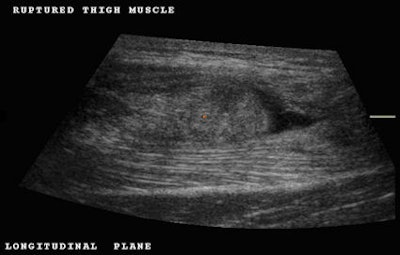

Initially, the examination of this patient was performed using traditional 2D ultrasound and subsequently with 3D ultrasound. Longitudinal scanning demonstrated the most distal portion of the rectus femoris muscle retracted with a swollen blunt end as a result of avulsion (Fig. 1). Active flexion of the thigh associated with extension of the leg causes the anterior mass to become more evident due to muscle contraction; this was observed in real-time ultrasound scanning. However, in order to permit patient comfort, 3D volume acquisition was performed with the patient in a relaxed position.

Partial avulsions are recognized as focal fusiform hypoechoic areas within the muscle. Longitudinal ultrasound images are well suited for evaluating deep distal aponeurosis tears and clearly demonstrate the retracted fibroadipose septa lying at a variable distance from their normal anatomical site of attachment into the aponeurosis.

The gap caused by the tear may be filled with fluid or hypoechoic tissue related to hemorrhagic infiltration. Complete tears of the rectus femoris with detachment of the muscle from the quadriceps tendon are more frequently detected with ultrasound. These appear as a complete separation of the muscle belly, which assumes a rounded and irregular distal shape instead of its classical pointed end. Acute cases demonstrate a hypoechoic blood collection distal to the torn muscle and superficial to the thickened and irregular deep distal aponeurosis.